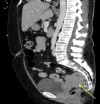

Figure 1

Figure 1. Sagittal CT showing heterogeneously enhancing presacral, posterior lower uterine soft tissue mass (yellow arrow) measuring 6.7 x 5.0 x 6.2 cm.